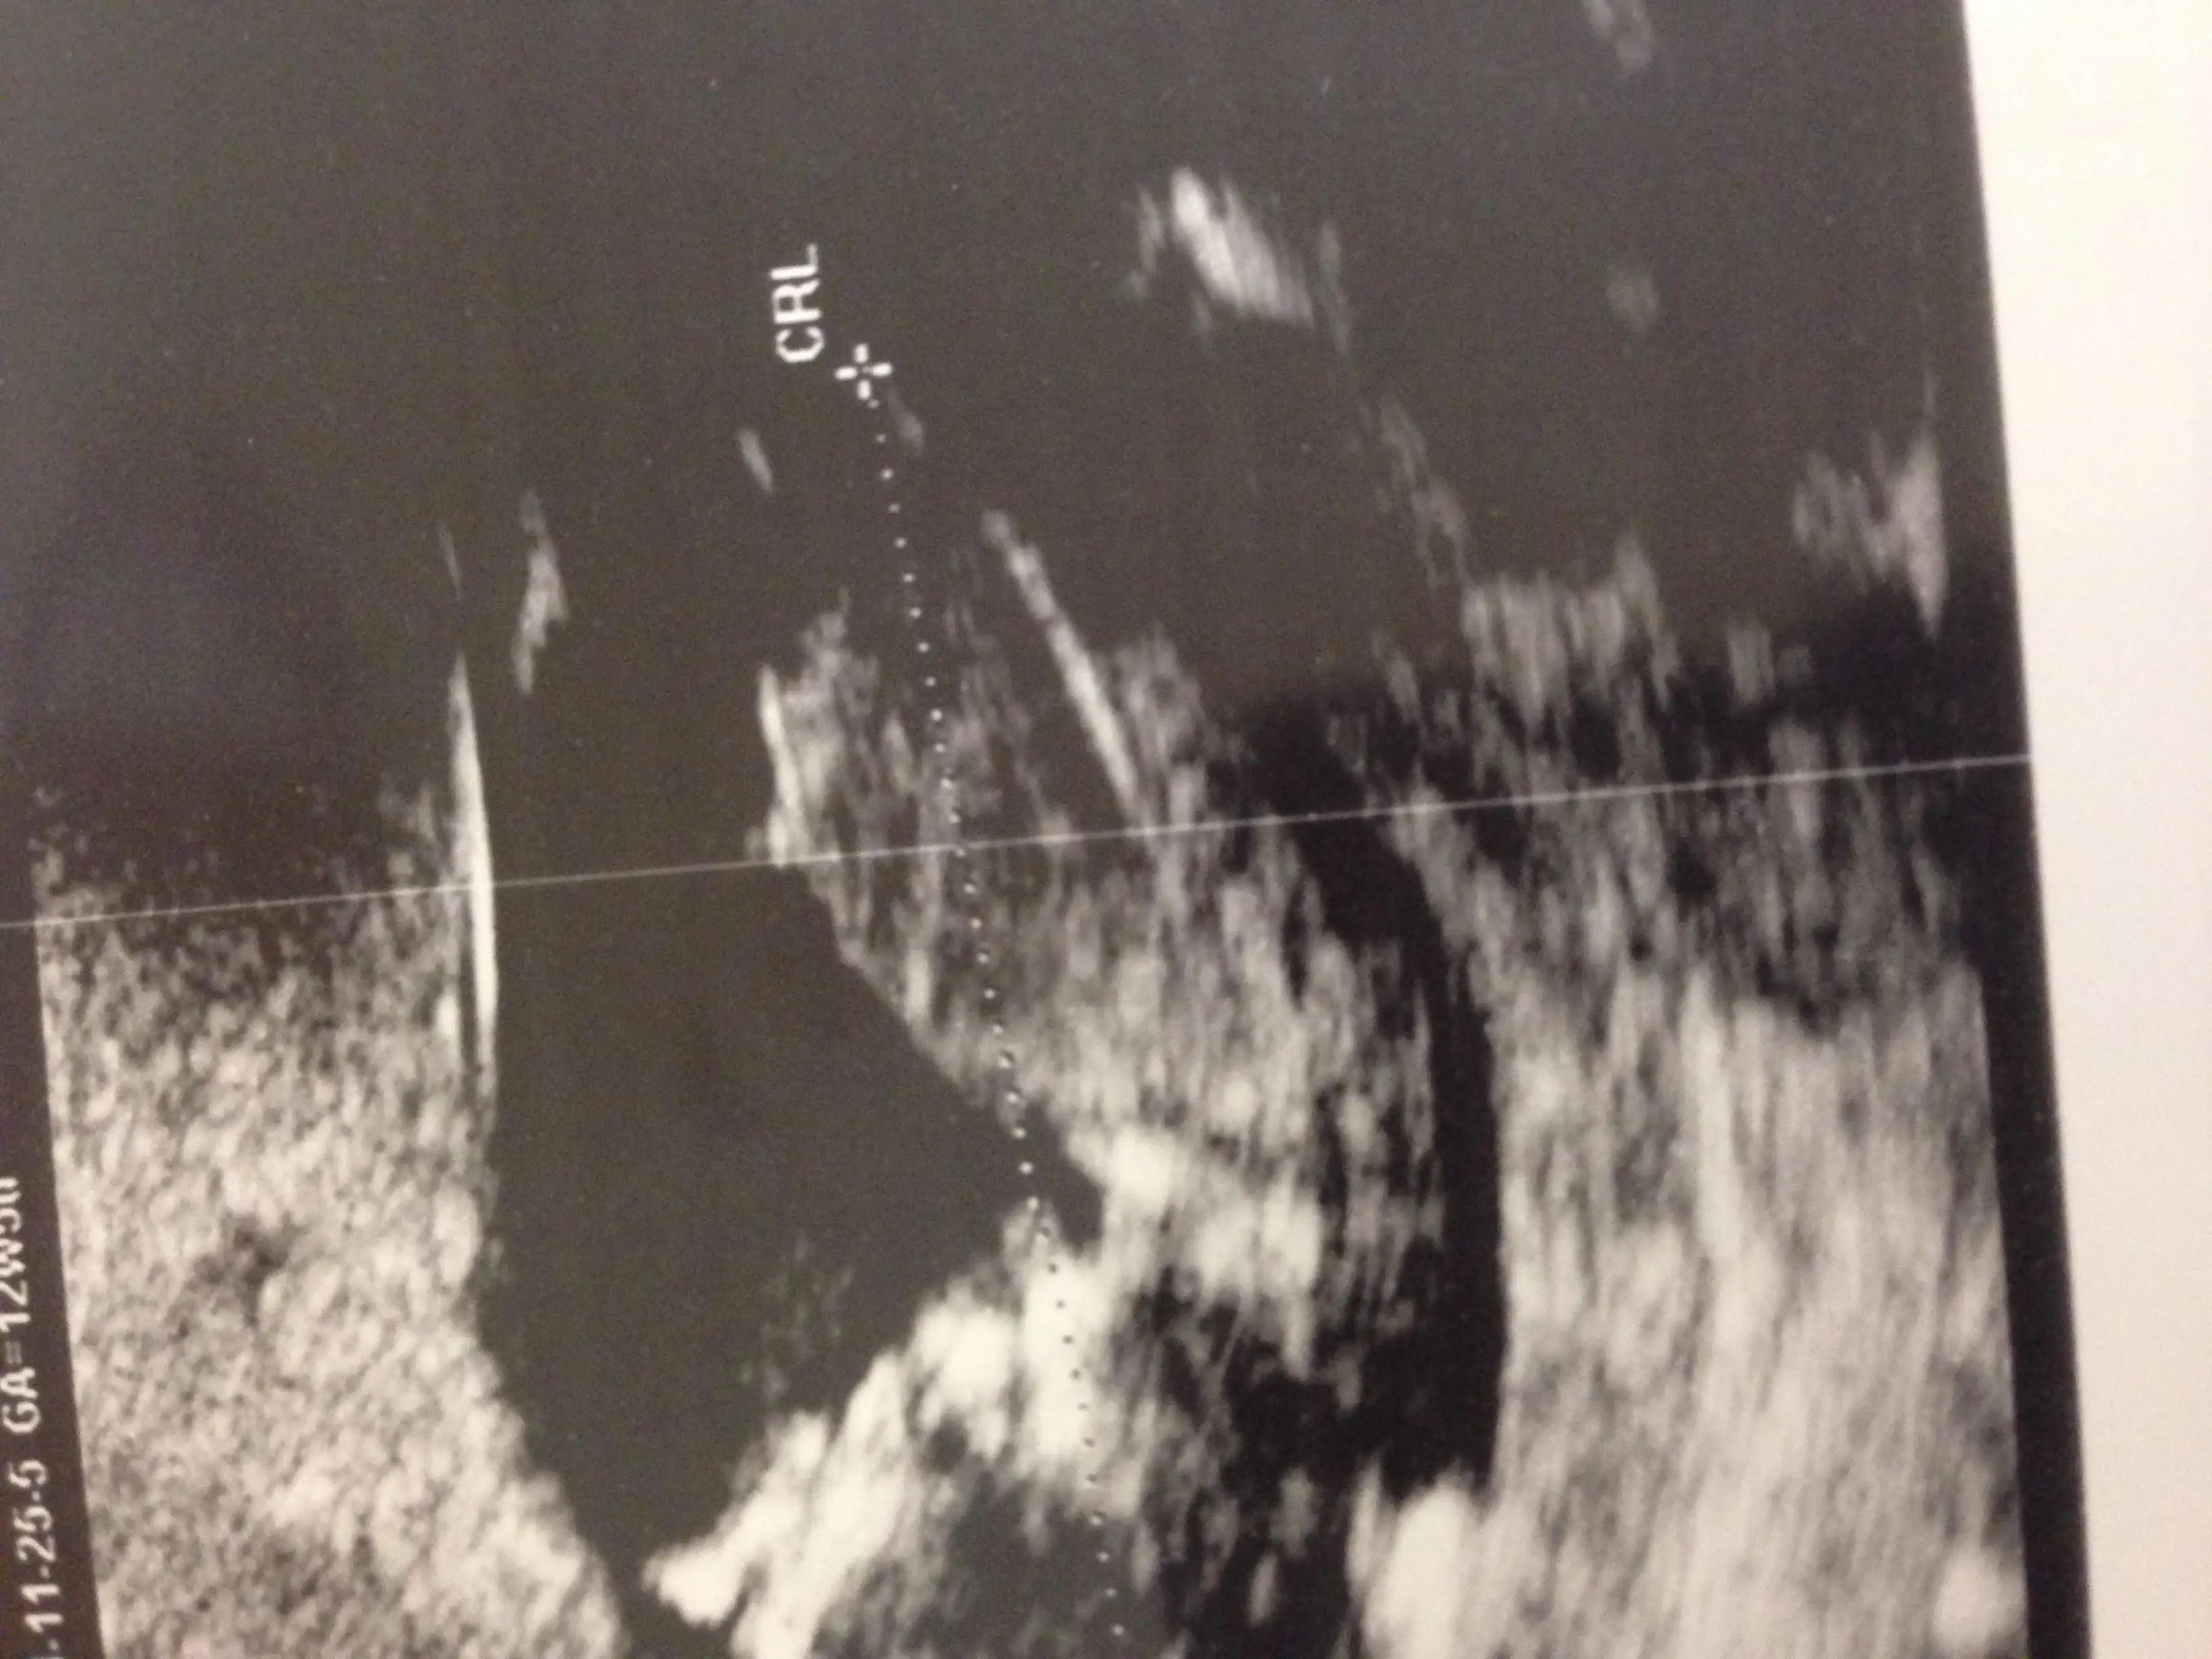

Canim resmini nub teorisi sayfasinda paylasayim bakalim ne dicekler orkidemde orda gorurse cvp verir haber ederimdenizkinub7 .!.:Canim esim bebisi videoya cekmisti ordan kopyaladigim bir resmi ekledim doktorun tam cikintisini isaretleyip gosterdigi yerin resmi. Onuda paylasmak istedim bi bakarsin tekrar doktorla ayni fikirdemisiniz merak ettim senin yorumunudaEki Görüntüle 1311947 Eki Görüntüle 1311948 Eki Görüntüle 1311949